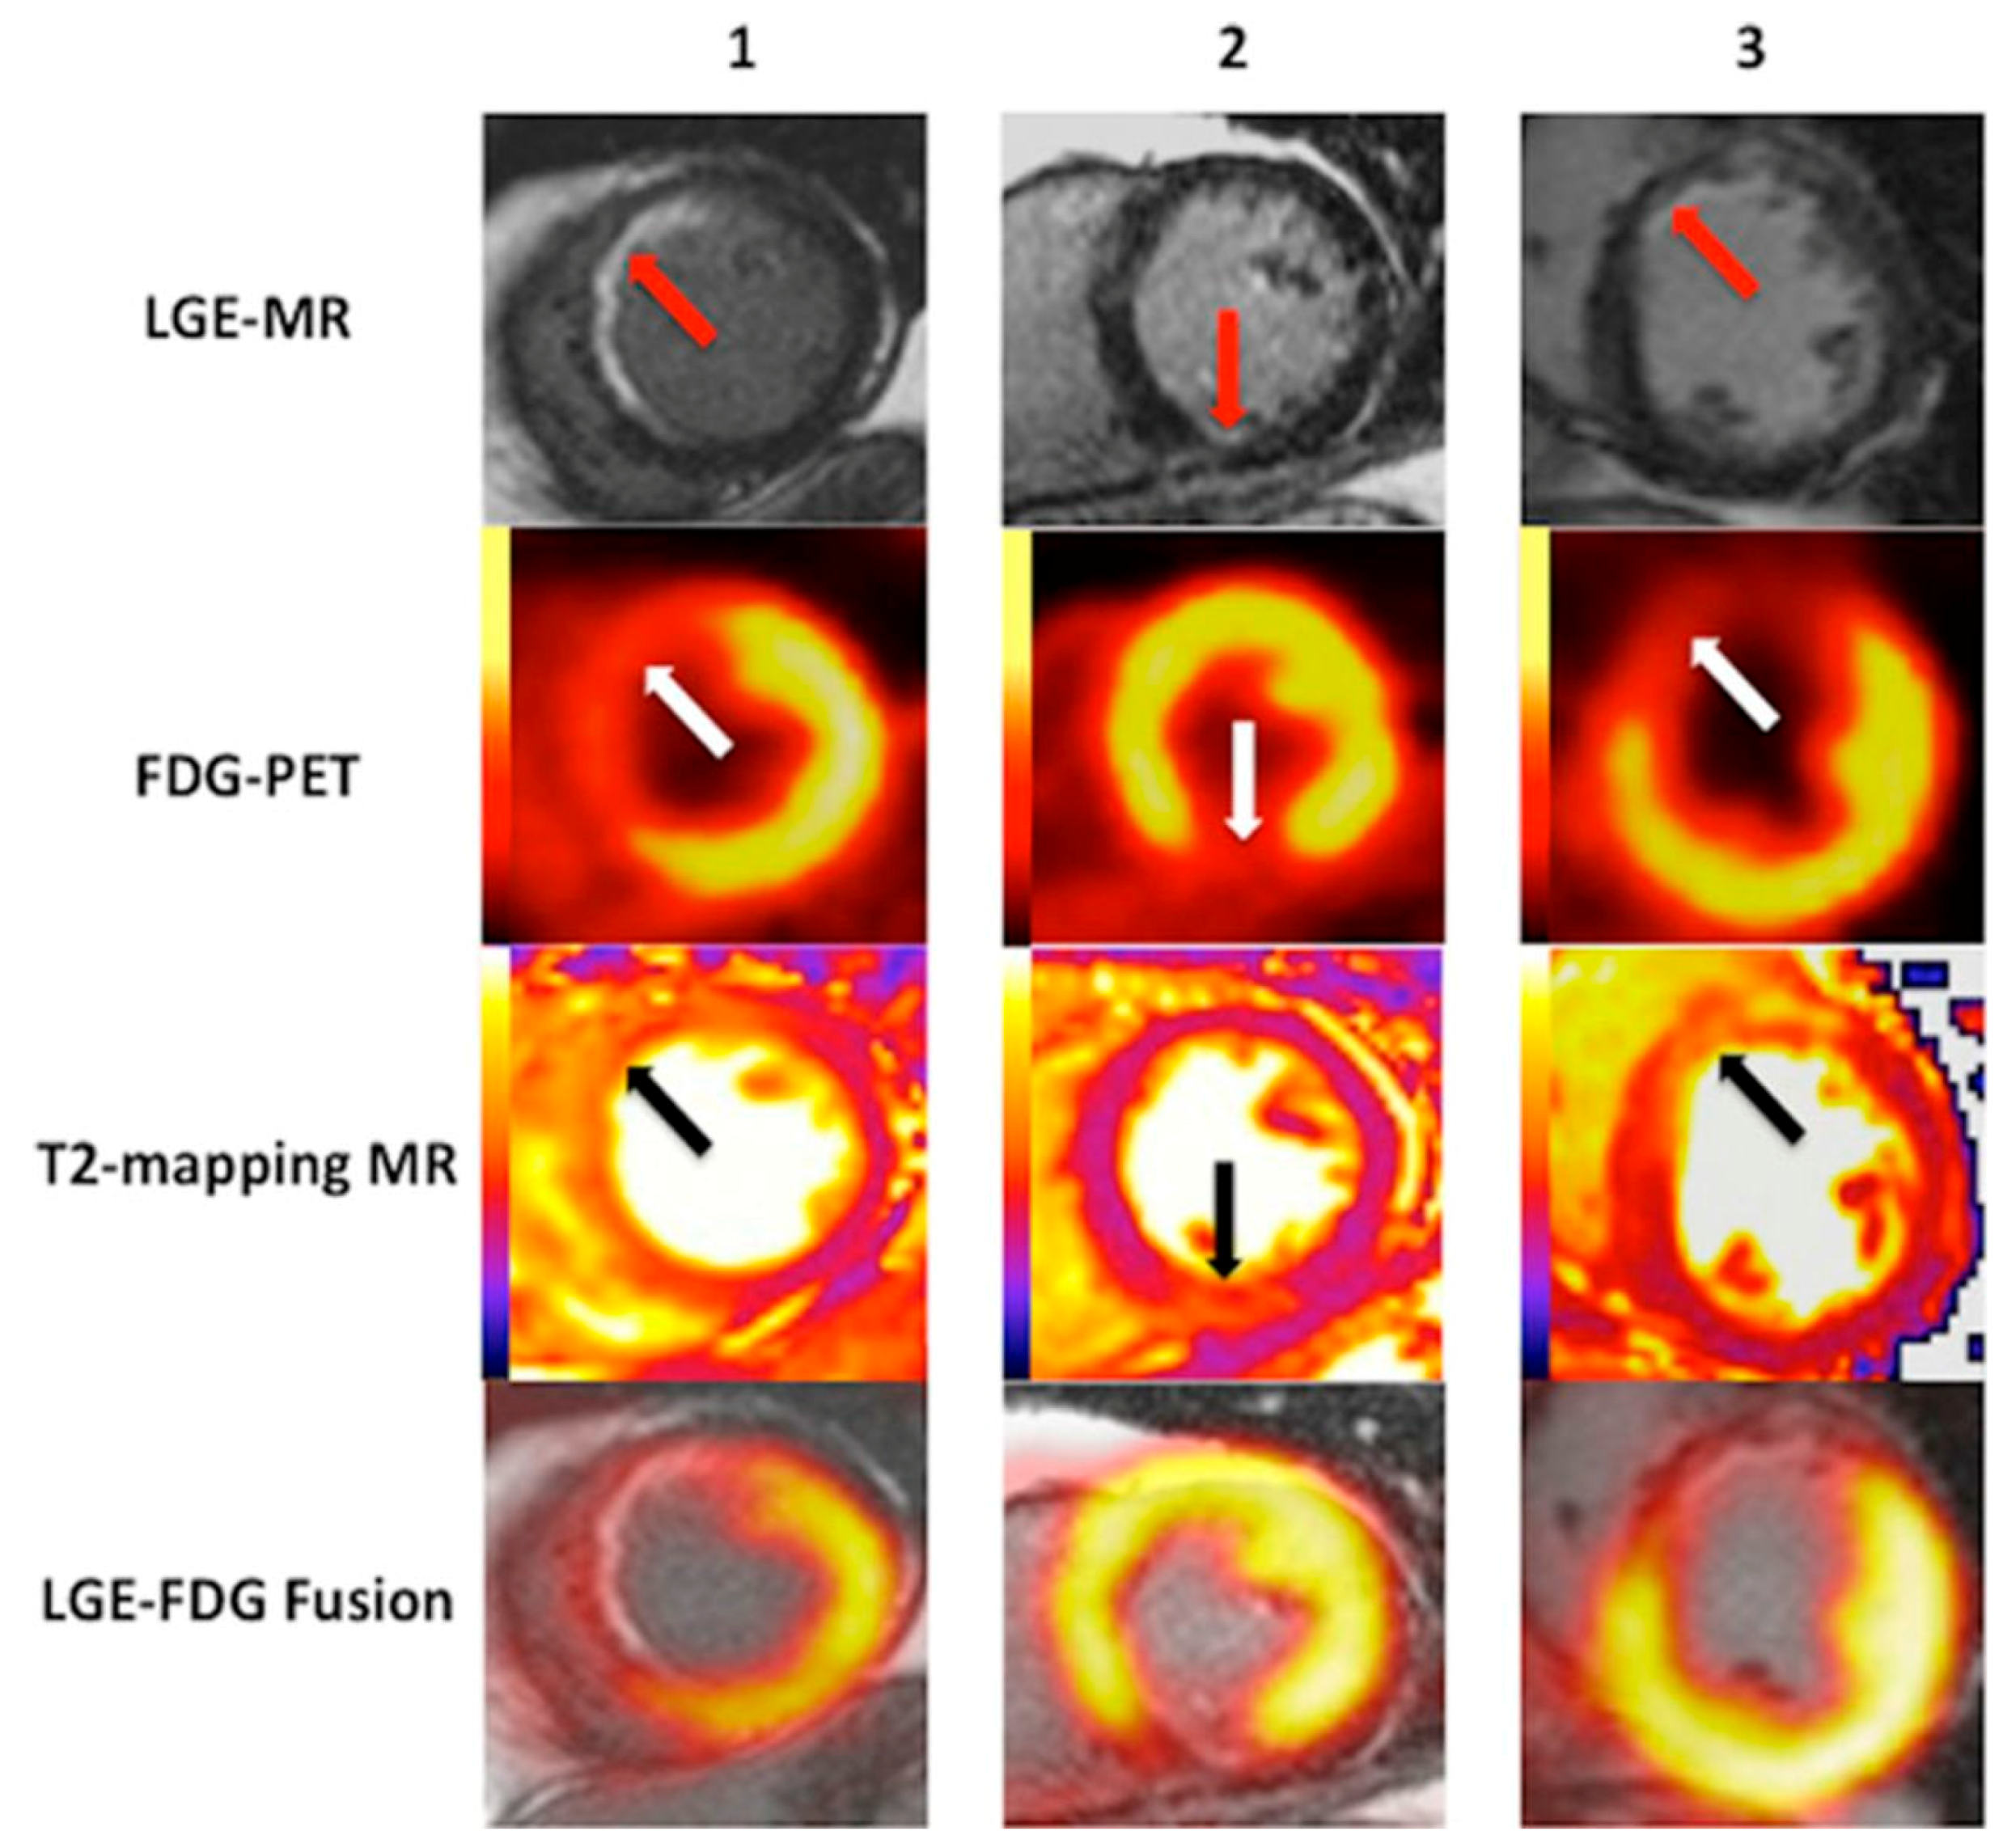

5.2. Viability and Infarct Assessment

5.3. Heart Failure